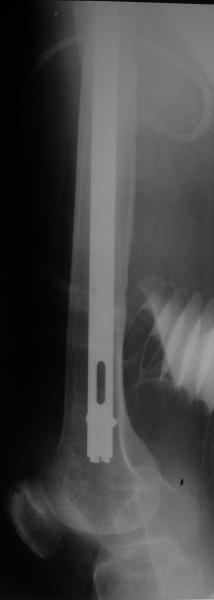

Reminded me of a case I did a couple years ago - 30 year old woman with juvenile rheumatoid arthritis and a nonunion below her stem. Fixed with retrograde nail which docked with the stem and a lateral locking plate. Image attached. One of the companies should come up with a stem design and nail system that anticipates this need.

Female, rheumatoid, THA in 2003, car accident in 2006, failed plating. Nailing in Oct 2007. The nail is solid with hollow proximal part where the stem is docked. Last images are in 1 year after

nailing.